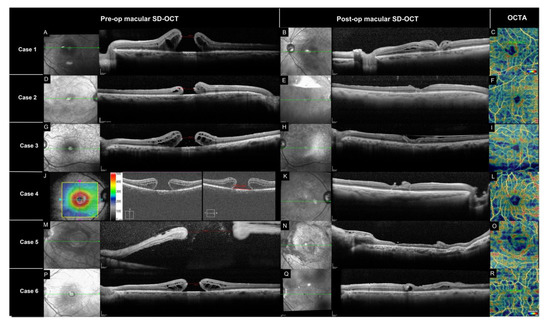

| Case | Gender | Age | Pre-Op VA (logMAR) | Post-Op VA (logMAR) | BD (mm) | MLD (mm) | AIO (mm) | # of Prior Surgeries |

|---|---|---|---|---|---|---|---|---|

| 1 | M | 70 | 0.6 | 1 | 1302 | 593 | 726 | 2 |

| 2 | F | 69 | 0.69 | 0.69 | 698 | 597 | 705 | 1 |

| 3 | F | 67 | 0.87 | 0.87 | 1392 | 634 | 818 | 1 |

| 4 | F | 67 | 1.77 | 1.3 | 1552 | 851 | 1229 | 1 |

| 5 | M | 35 | 1.3 | 1.24 | 8449 | 2188 | 2381 | 0 |

| 6 | M | 74 | 0.69 | 1 | 1266 | 590 | 841 | 1 |

| Mean | 63.7 | 0.99 | 1.02 | 2443 | 909 | 1117 | 1 |

| Case | Vascular Density Study Eye (%) | Vascular Density Fellow Eye (%) | FAZ Area Study Eye (mm2) | FAZ Area Fellow Eye (mm2) |

|---|---|---|---|---|

| 1 | 17.84 | 17.61 | 156.4 | 45.4 |

| 2 | 25.4 | 19.90 | 57.0 | 45.8 |

| 3 | 24.99 | 32.67 | 69.1 | 25.4 |

| 4 | 28.02 | 22.42 | 128.1 | 41.5 |

| 5 | 33.5 | 12.18 | 320.0 | 56.0 |

| 6 | 38.86 | 16.45 | 56.3 | 34.9 |

| Mean | 28.10 | 20.20 | 131.2 | 41.5 |